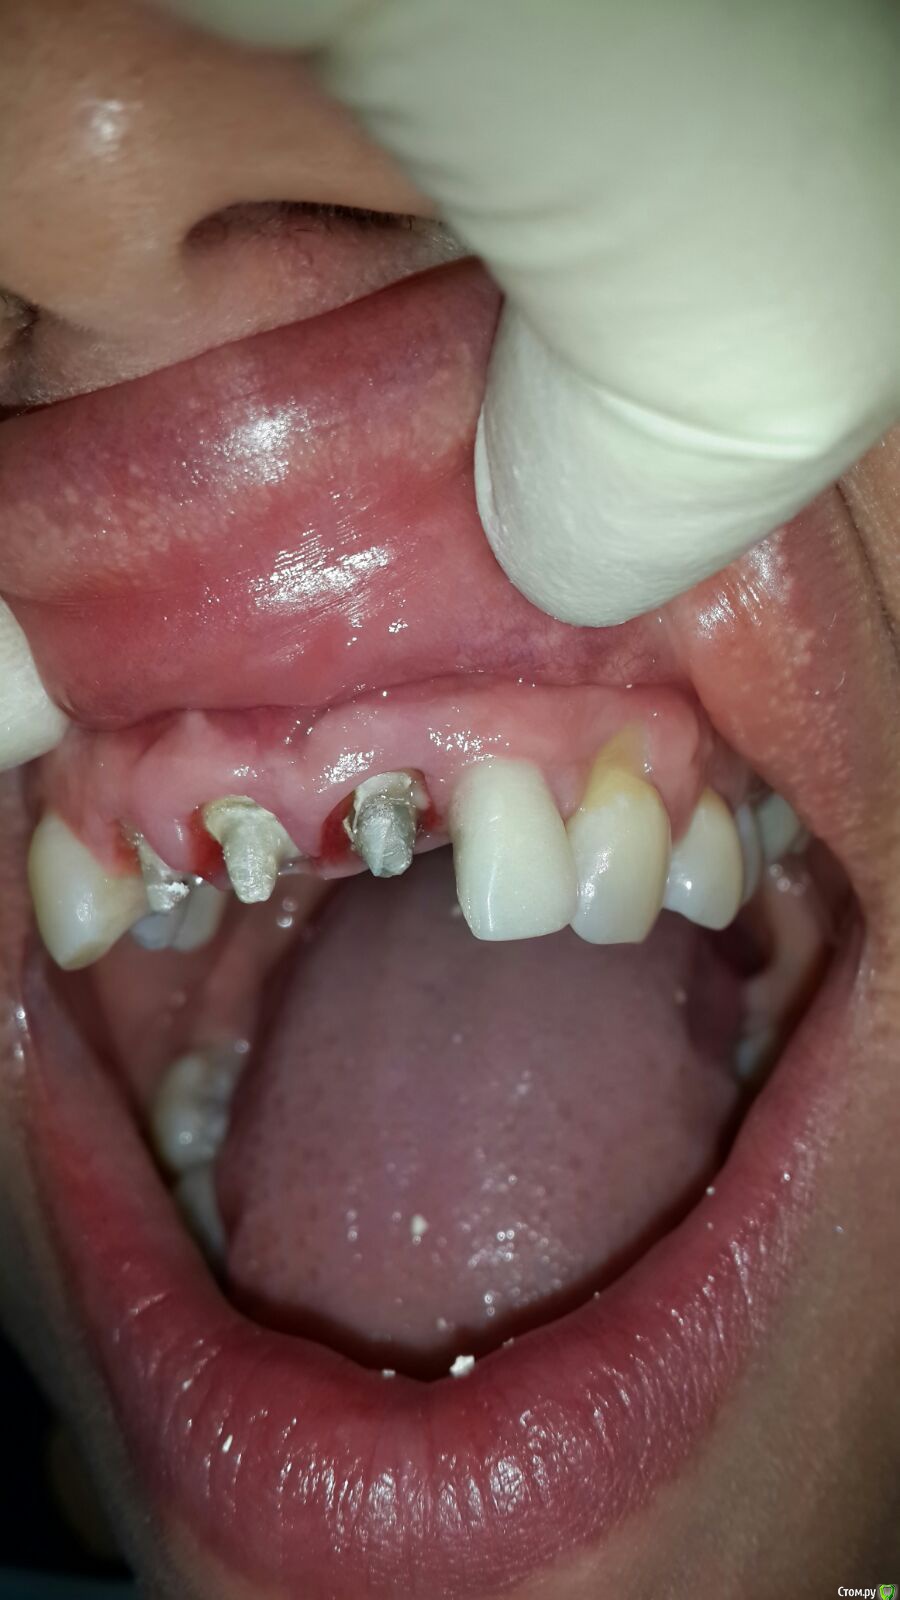

victor57 Опубликовано 21 октября, 2015 Поделиться Опубликовано 21 октября, 2015 (изменено) Привет.сегодня пришла пациентка на этапе.ведем её уже год. Отсутствовал 2.2. Провели аугментацию,потом имплантации.на 12,11,21 коронки уже более 5 лет. Провели одновременно с установкой формироваться убп на 12,11 зубах. Сейчас вопрос по сосочек между 21,22.Ортопед говорит,что времянками по максимуму отдавил.что посоветуете? Изменено 21 октября, 2015 пользователем victor57 Ссылка на комментарий

victor57 Опубликовано 22 октября, 2015 Автор Поделиться Опубликовано 22 октября, 2015 Планировал ССТ сажать Ссылка на комментарий

Дмитрий Никитюк Опубликовано 22 октября, 2015 Поделиться Опубликовано 22 октября, 2015 Снимок нужен. Но и без него видно, что одна из проблем, это близкое расположение имплантата к зубу 21. С мягкими тканями работать нужно, но идеального результат получиться добиться разве что заглушив имплантат. Как более компромиссный вариант можно рассмотреть ортодонтическую коррекцию положения зуба 21. 2 Ссылка на комментарий

carloss Опубликовано 23 октября, 2015 Поделиться Опубликовано 23 октября, 2015 Олег, там гдн нет места, это рядом с клыком и там сосочек пока в полном порядке.. Но чтобы он более менее остался в будущем, стоит заменить абатмент и коронку, и постараться дать там макимально места.. Медиально же место есть Ссылка на комментарий

Дмитрий Никитюк Опубликовано 23 октября, 2015 Поделиться Опубликовано 23 октября, 2015 Вот снимок.расстояние оптимальное на мой взгляд.Странная проекция снимка. Складывается впечатление, что имплантат стоит вплотную к клыку. Или так и есть? Если да, то тогда нужно поработать с профилем времянки. Ссылка на комментарий